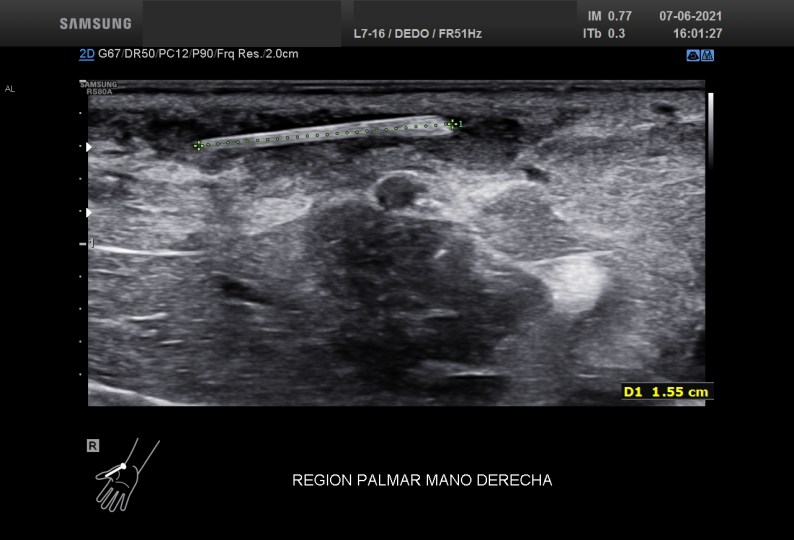

Para que te puedas hacer una idea del tamaño de la espina de la palmera, te muestro esta imagen que demuestra un tamaño aproximado a 1,5 centímetros de longitud. Lógicamente también realicé la medida en eje corto y luego para finalizar, realicé una medida muy valiosa en caso de que estos cuerpos extraños deban ser extraídos y que es la distancia que existe desde la piel hasta el objeto en cuestión.

La distancia desde la piel corresponde a 0,23 cms. El paciente fue remitido al cirujano y fue intervenido para desalojar el cuerpo extraño.